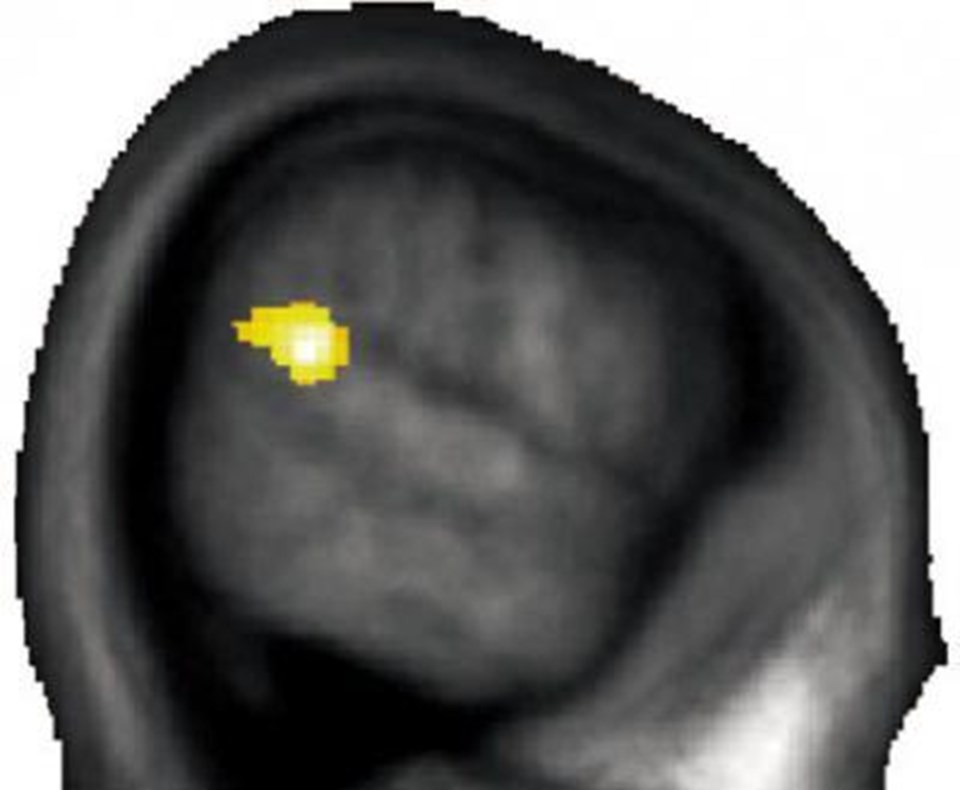

Parietal ve temporal lobun kesişimi olan bölge.

Parietal ve temporal lobun kesişimi olan bölge.

Beyindeki bu bölgenin, bir başkasının hislerini ve düşüncelerini anlamada daha önemli olduğunu fark eden bilim insanları, fedakarlığın iki lobun kesişiminde biçimlendiğini gördü. Araştırmada yer alan Yosuke Morişima, “Deneyde diğerlerine göre daha fedakar davranan insanların, iki lob arasında daha fazla gri maddeye sahip olduğunu gördük” dedi.